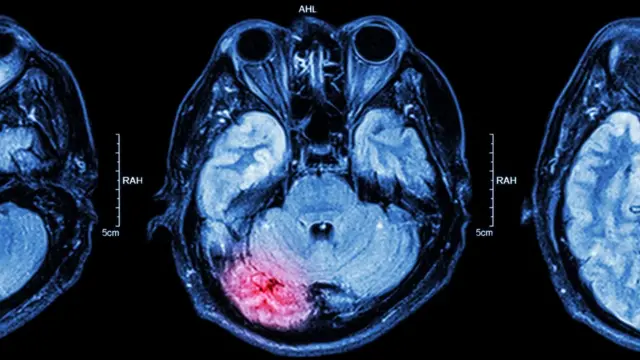

El Estado de Mínima Conciencia (EMC) es una condición de una conciencia severamente alterada, donde hay una evidencia mínima de cualquier forma de conocimiento de sí mismo y su entorno.

La condición puede surgir cuando alguien sale de un coma hacia lo que se conoce como estado vegetativo, donde se está "despierto" pero no consciente de sí mismo o el entorno.

Alguien puede entrar en coma cuando las fibras nerviosas en lo profundo del cerebro, que normalmente mantienen a la persona alera y consciente, se dañan. Esto puede suceder por una lesión cerebral severa causada por un accidente u otro factor como una infección o derrame.

A diferencia del EMC, el paciente no puede ser despertado, no manifiesta respuesta alguna al mundo exterior y sus ojos no se abren independientemente. No hay respuesta a las sensaciones internas como hambre o dolor, o a los estímulos externos como el ruido.